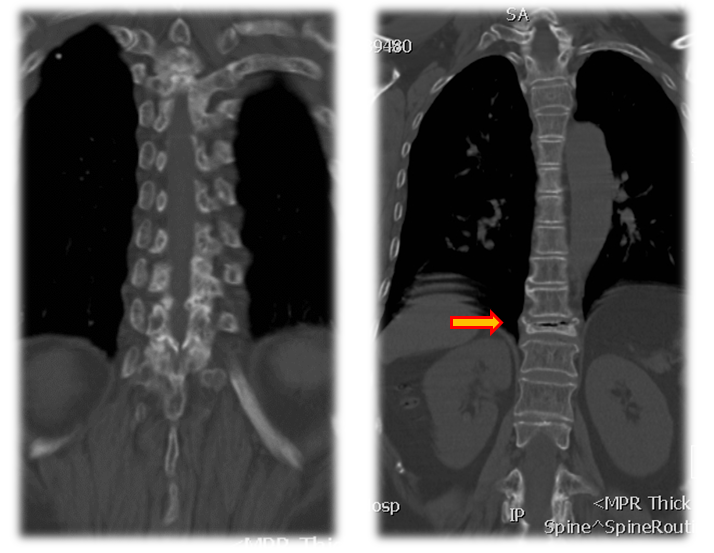

术前CT

术前诊断:1.胸腰椎后凸畸形,2.重度骨质疏松症,3.Kummell病II期,4.胸椎椎管狭窄,5.黄韧带骨化症,6.高血压病。

手术治疗:T10-T12棘突椎板切除;T11 截骨后凸矫形;T9-L1椎弓根固定,均为骨水泥螺钉,安放横联两根;T10/11及各椎板后方大量植异体骨及自体骨。

术后X线

术后CT